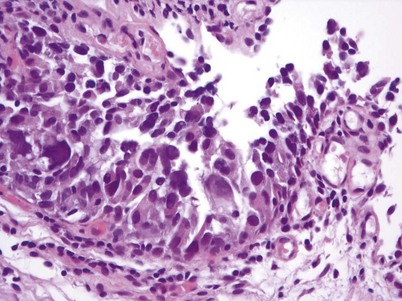

There are key genetic and phenotypic changes that occur in cancer cells, thus providing the ability to invade the underlying stroma. Invasive urothelial carcinoma is divided into two groups: lamina propria and deep muscle invasion. Lamina propria invasive tumors are high-grade cancers that can be in clusters or in single cells, with single-cell invasion having a worse prognosis (Fig. 80–11). Rarely, low-grade cancers can invade the lamina propria. Vascular invasion can occur within the lamina propria because of the large vascular network within this tissue layer; however, it is frequently overcalled because of retraction artifact around tumor nests. There is a subdivision of lamina propria invasion into T1a (invasion above muscularis mucosa) and T1b (invasion below the muscularis mucosa). This subject will be dealt with more extensively in the Staging section.